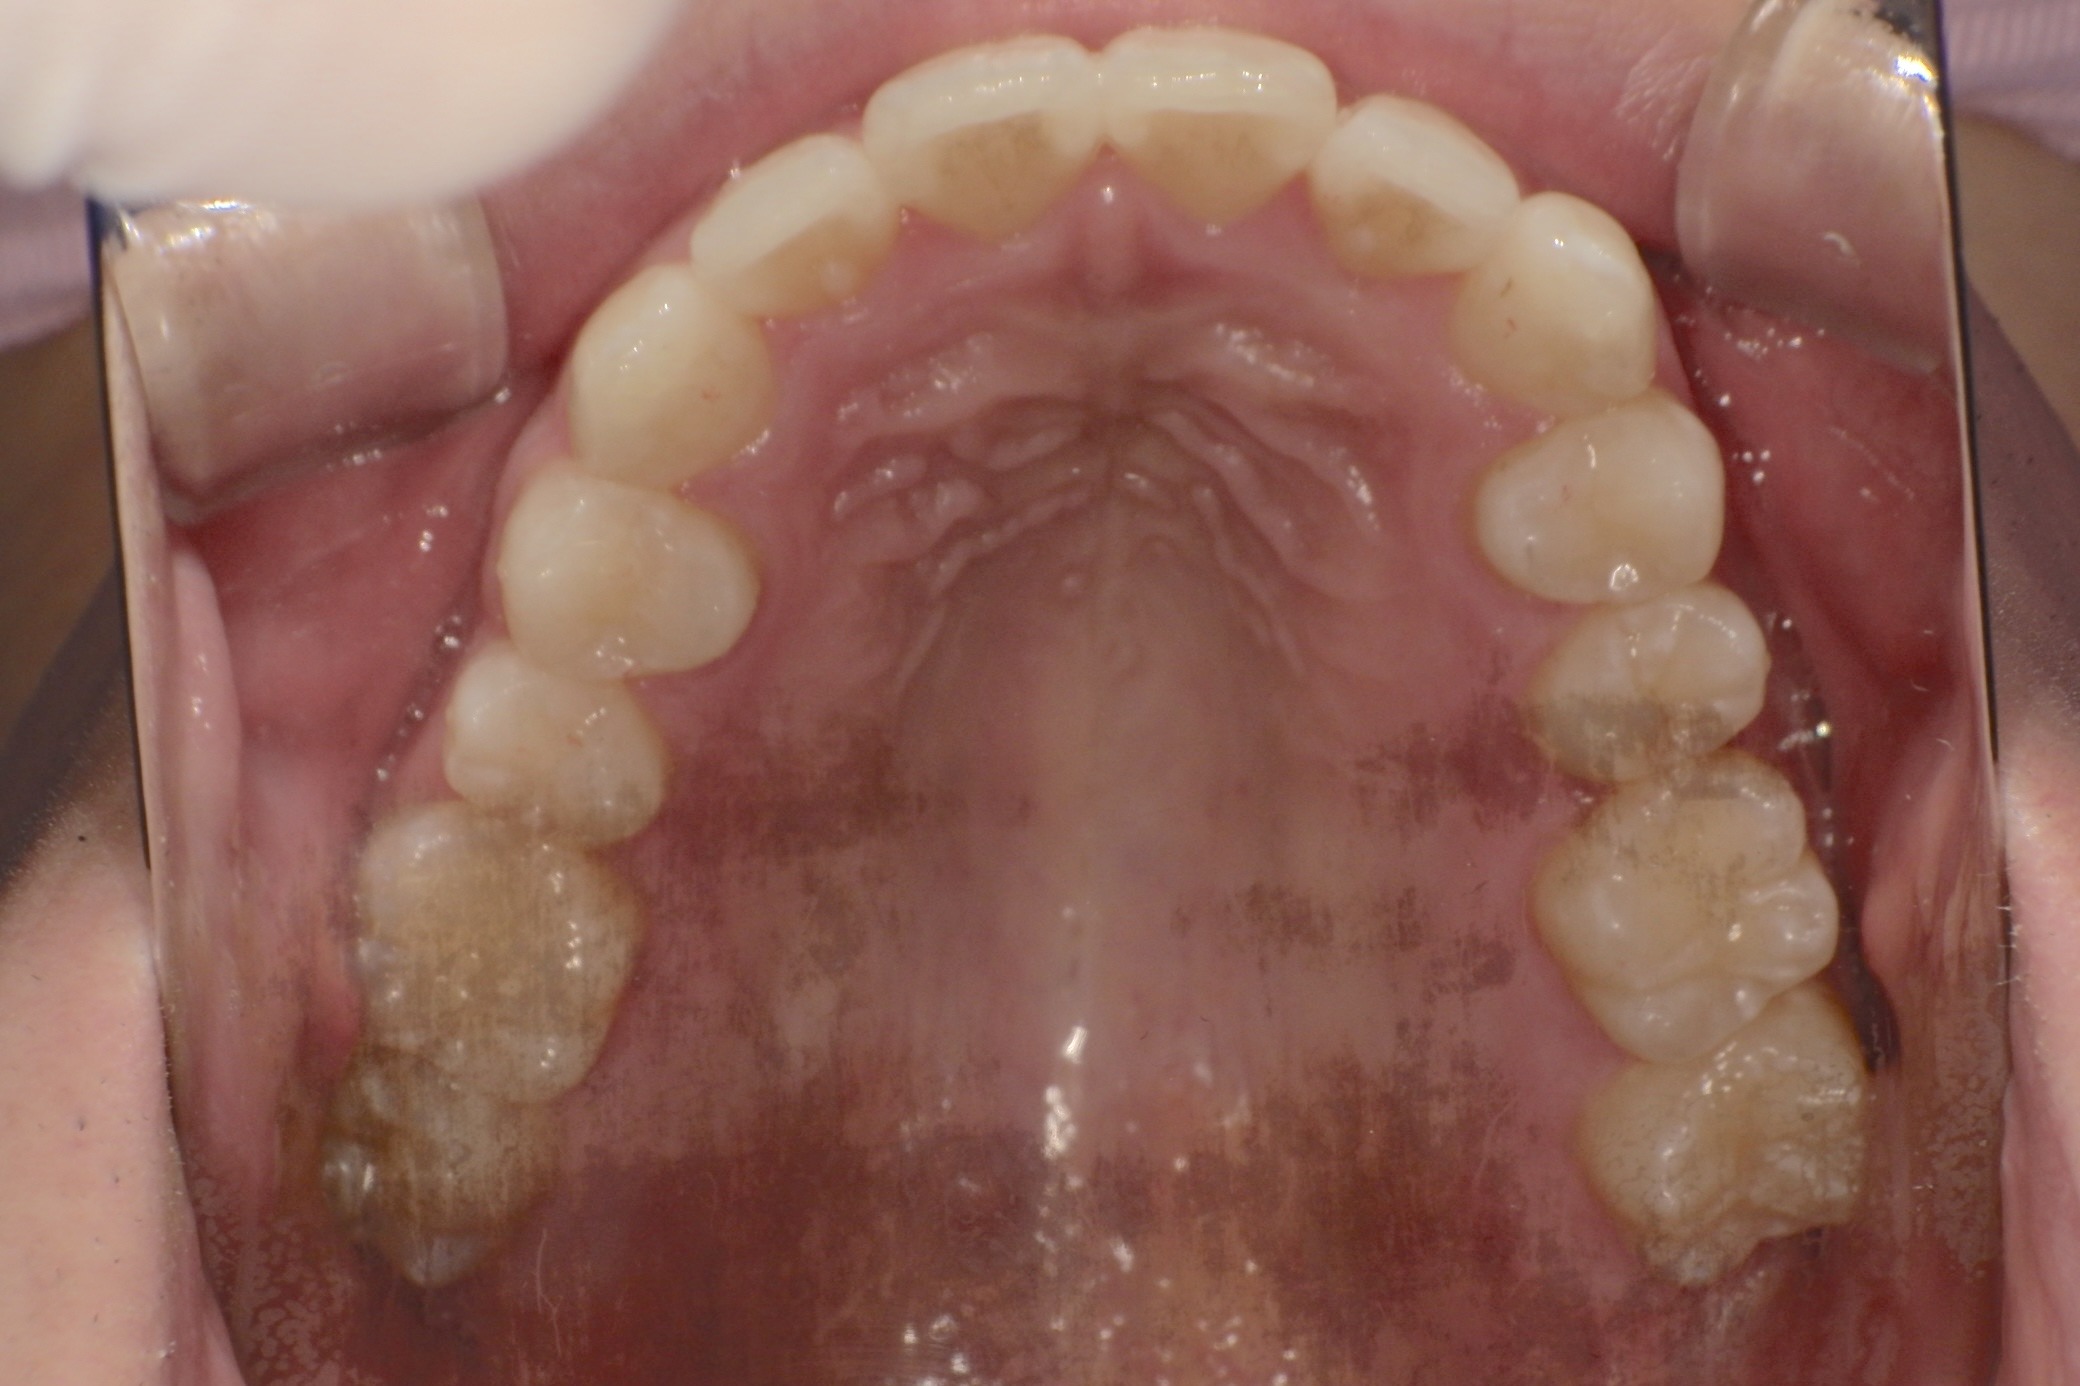

人と接する機会が多く、第一印象を大切にしたいと考え、写真写りや笑顔への自信を高めたいという思いから矯正を決意された矯正当時学生だった22歳男性の H.S.様に、スマイルモア矯正を選んだ理由を伺いました。

| 費用 | 360,000円(税込396,000円) |

| 治療期間 | 11ヶ月 |

| 治療内容 | マウスピースを用いた歯列矯正 |

| 追加処置 | IPR |

以前よりも歯並びが改善され、人とコミュニケーションをとることに自信がつきました。 「スマイルモア」という名前の通り、笑顔に自信がついたことで今までよりも口を開けて笑う機会も増えました。 矯正期間が年単位だったのですぐに変化があったわけではないですが、綺麗な仕上がりに満足しています。